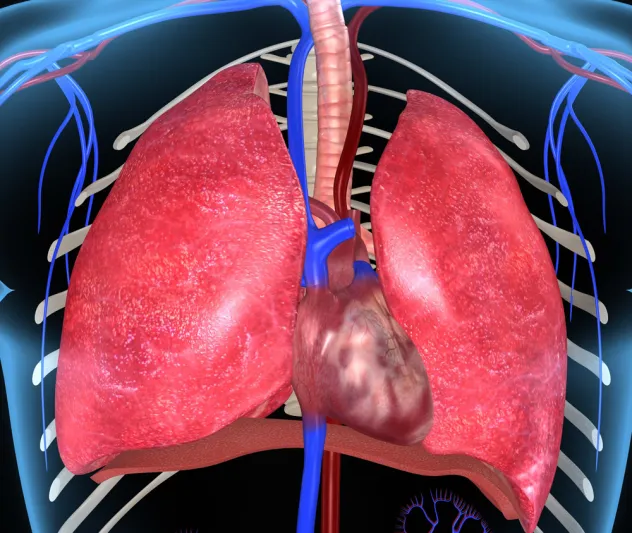

القلب على الجانب الأيمن

١ من كل ١٠٠ ألف شخص حول العالم يملك قلبه على الجهة اليمنى عوضاً عن الجهة اليسرى. الخبراء لا يعدون الأمر تشوهاً خلقياً بل يمكن للشخص أن يكمل حياته بشكل طبيعي ويقوم بما يقوم به كل البشر سواء لناحية المهن أو الرياضة أو غيرها. القلب عندما يكون على الجانب الأيمن يكون مثل المرآة، إذ يمثل إنعكاسا كاملا، ويكون إتجاه رأس القلب إلى اليمين، مع انعاكس كامل في الشرايين الرئيسية.التكوين الفسيولوجي لجسم الإنسان يؤدي أحيانا إلى وجود مثل هذه الحالات وإنعكاس لموقع الأعضاء، ففي حالة وجود القلب على الجانب الأيمن من الجسم تكون بقية أعضاء الجسم معكوسة أيضا مثل الكبد.